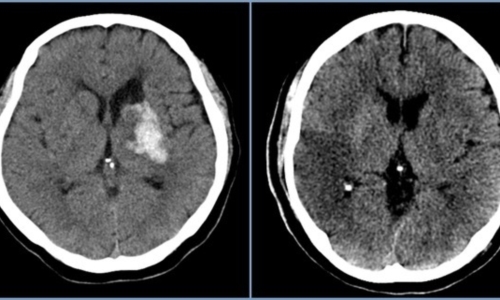

뇌혈관이 막히거나 터지는 질환을 통칭하는 것이 뇌졸중이고 그 중 뇌혈관이 막히는 것이 뇌경색 그리고 뇌혈관이 터지는것을 뇌출혈이라고 합니다. 뇌졸중은 영구적인 손상이 많고 증상에 따라 전신이나 신체 일부 기능이 마비되는 등의 심각한 후유증이 남는 무서운 질병인데요 오늘은 뇌경색 초기증상 및 뇌경색 치료방법에 대해 알려드리겠습니다.

신체가 건강해도 뇌에 문제가 생기게 되면 신체 기능을 제대로 할 수가 없게 됩니다. 뇌 손상으로 제한된 신체 기능은 치료를 마친 후에도 회복이 제대로 되지 않거나 장애로 남는 경우가 많은데 뇌조직이 괴사되며 발생하게 되는 뇌경색이 대표적입니다. 과거에는 뇌출혈 환자가 많았지만 현재는 전체 뇌졸중 환자의 약 60~70%가 뇌경색 환자인 만큼 뇌졸중에서도 뇌경색이 차지하는 비중이 크다고 합니다.

뇌졸중에서도 혈관이 막히는 뇌경색이야말로 촌각을 다투는 응급질환이라고 볼 수 있습니다. 뇌혈관이 막히면서 점차 뇌세포가 괴사하기 때문에, 증상 발현 3시간 안에 혈전용해제를 투여하고 시술에 들어가야 심각한 상황을 면할 수 있습니다. 뇌경색 치료방법에 있어 가장 중요한 것은 혈전을 녹이는 혈전용해제를 정맥 투여함으로써 막힌 혈관을 뚫어주는 것입니다. 하지만 혈전용해제의 경우도 출혈 가능성이 있는 환자에게는 투여할 수 없으며, 또한 혈소판 수치가 낮아서 지혈이 되지 않는 경우에는 제외된다고 합니다.